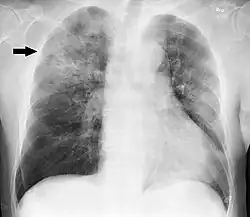

Clinical features of a respiratory tract infection may include initial symptoms of an upper respiratory tract infection mimicking a viral infection, usually associated with low-grade fevers. This may progress to the lower respiratory tract within a few days, with features often resembling those of wheezy bronchitis. Sputum may be difficult to expectorate and is often grey or creamy in color. The cough may persist for weeks without appropriate treatment. Many cases are diagnosed after presenting chest infections that do not respond to penicillins or first-generation cephalosporins. A chest X-ray can identify alveolar consolidation.[36]

Clinical diagnosis of invasive H. influenzae infection (infection that has spread to the bloodstream and internal tissues) is typically confirmed by bacterial culture, latex particle agglutination tests, or polymerase chain reaction tests on clinical samples obtained from an otherwise sterile body site. In this respect, H. influenzae cultured from the nasopharyngeal cavity or throat would not indicate H. influenzae disease, because these sites are colonized in disease-free individuals.[37] However, H. influenzae isolated from cerebrospinal fluid or blood or joint fluid would indicate invasive H. influenzae infection. Microscopic observation of a Gram stained specimen of H. influenzae will show Gram-negative coccobacillus. The cultured organism can be further characterized using catalase and oxidase tests, both of which should be positive. Further serological testing is necessary to distinguish the capsular polysaccharide and differentiate between H. influenzae b and nonencapsulated strains.